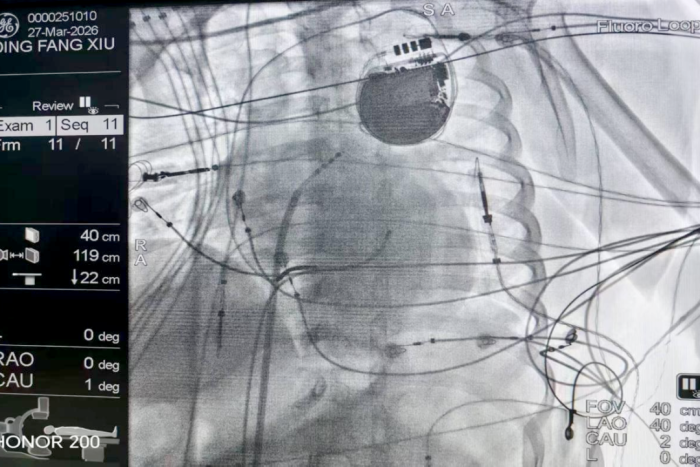

图片 3.png

透视下ICD术后患者导管消融图